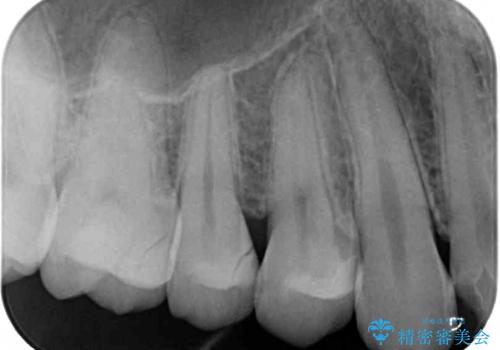

- 以前治療した詰め物が外れてしまい、冷たいものがしみることを主訴として来院された患者様です。

むし歯がないことを確認し、セラミックインレーにて修復するととしました。

適合の良いセラミックインレーの装着により、冷たいものがしみる症状はなくなりました。